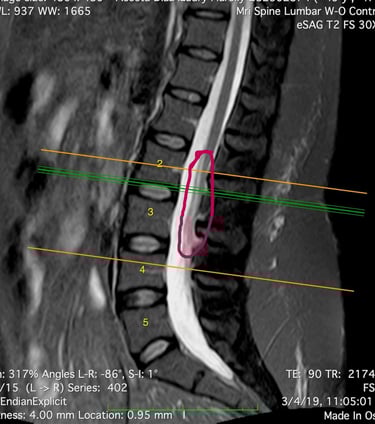

That MRI resulted on the finding of a syrinx, which is a cyst inside the spinal cord (Syringomyelia), full of cerebroespinal fluid (CSF) and obstructing the canal. The radiologist also found the fusion of two cervical vertebraes (Klippel-Feil) and led her to see a neurosurgeon who said he didn't have the experience to treat her but assured her symptoms were not related to this finding.

Her symptoms list continued to increase (weakness, numbness, dizziness, palpitations and irregular heart rate) and so the number of doctors she would see, trying to find answers, and that's when she decided to have a consultation with a doctor in the US (in July 2021) who confirmed three diagnoses: Syringomyelia, Klippel-Feil and Tethered Cord. This last anomaly was found on MRI images she had from 2019, which had been seen by several doctors (radiologists, orthopedist, neurosurgeon and family doctor) but none of them were able to see the defect.

MRI imaging is often used to evaluate people with symptoms of TSCS. Doctors can use MRI imaging to diagnose where the tethering is located, whether the base of a patient's spinal cord (the conus medullaris) is lower than normal, or if a tumor or a fatty mass (known as a lipoma) is causing the symptoms of TSCS.